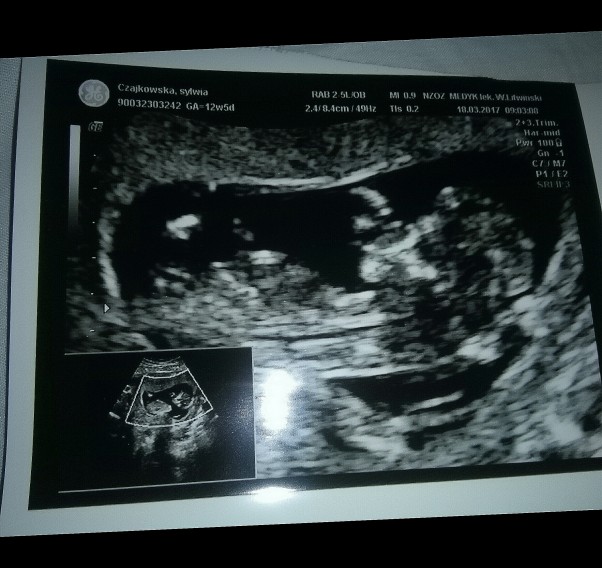

My juz jesteśmy po pierwszym usg genetycznym prawdopodobieństwo wad genetycznych bardzo male i co najpiekniejsze w tym wszystkim cale usg dzidzia ssala kciuk słodki widok :-)